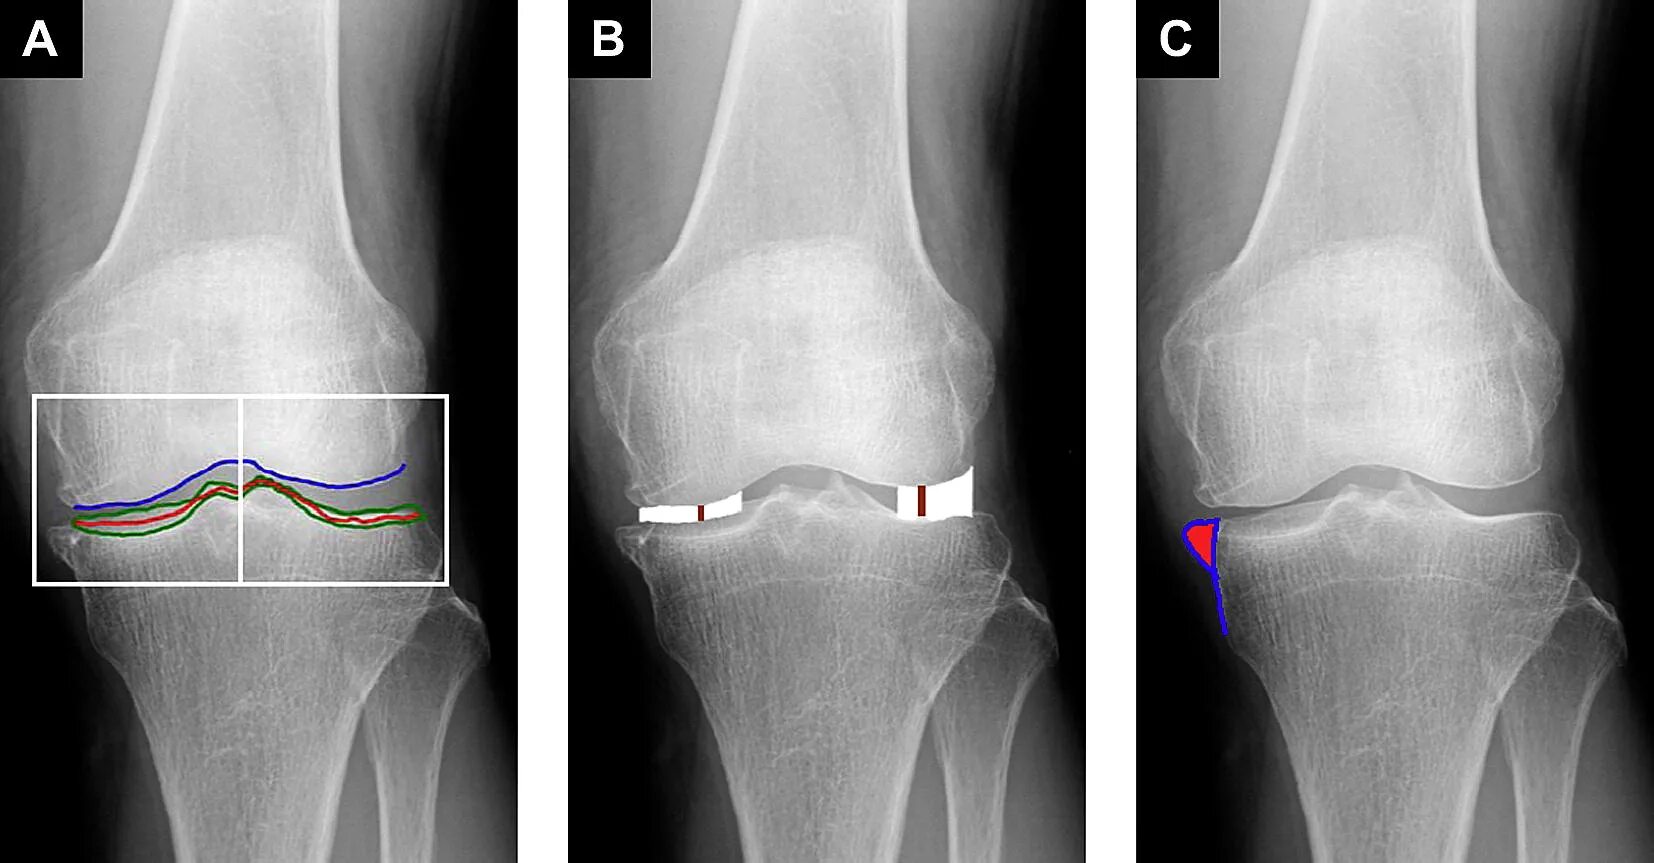

Остеоартрит 2025